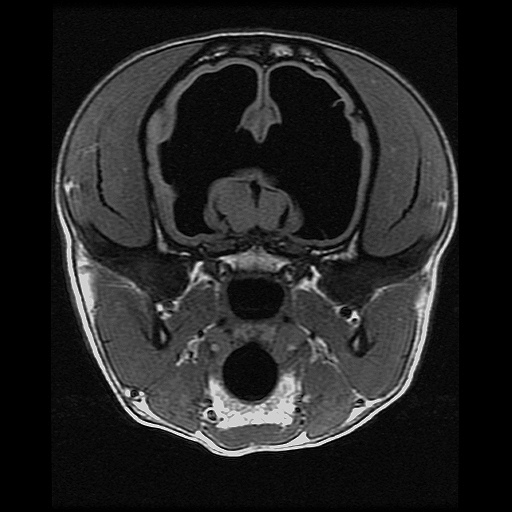

Transverse T1